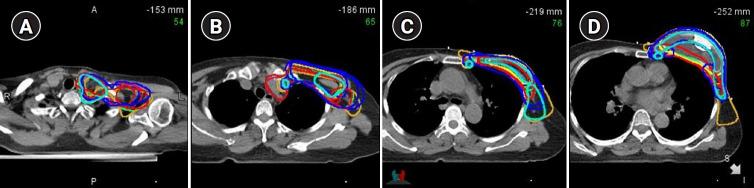

We identified the practice patterns and inter-hospital variations from a multi-center cohort of women with breast cancer who underwent post-mastectomy RT (PMRT) to the reconstructed breast at 16 institutions between 2015 and 2016. The institutions were requested to contour the target volume and produce RT plans for one representative case with five different clinical scenarios and answer questionnaires which elicited infrastructural information. We assessed the inter-institutional variations in RT in terms of the target, normal organ delineation, and dose-volume histograms.

Three hundred fourteen patients were included; 99% of them underwent immediate reconstruction. The most irradiated material was tissue expander (36.9%) followed by transverse rectus abdominis musculocutaneous flap (23.9%) and silicone implant (12.1%). In prosthetic-based reconstruction with tissue expander, most patients received PMRT following partial deflation. Conventional fractionation and hypofractionation RT were used in 66.6% and 33.4% patients, respectively (commonest: 40.05 Gy in 15 fractions [17.5%]). Furthermore, 15.6% of the patients received boost RT and 53.5% were treated with bolus. Overall, 15 physicians responded to the questionnaires and six submitted their contours and RT plans. There was a significant variability in target delineations and RT plans between physicians, and between clinical scenarios.